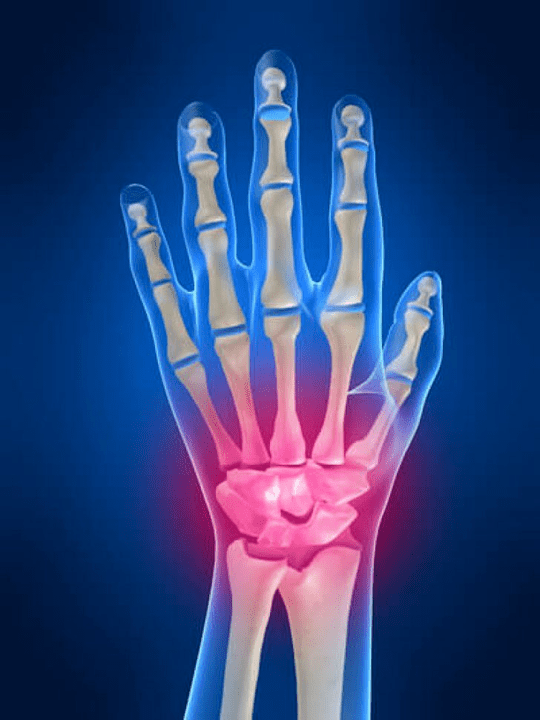

Joint painThe fingers are an indispensable sign of any joint pathology in which the structural components of these joints are damaged.First of all, the pain in the area of these joints can be associated with various autoimmune diseases (Systemic red lust, rheumatoid arthritis, psoriatic arthritis, etc.) in which immune factors cause damage to their joint tissues.

The next main reason that can startPainIn the joints of the fingers, there may be injuries (Bruises, dislocations, bone fractures, ligaments).Pain in these joints can also be caused by degenerative changes that occur in their joint tissues.This can often be observed with osteoarthritis.

Which structures can inflame themselves in the joints of the hands?

Inflammation is a typical pathological process characteristic of those tissues and organs that have been damaged for any reason.It is worth remembering that, in most cases, every disease (For example, gout, rheumatoid arthritis, etc.) or trauma that damage the joints of the hands to one degree or another, affect not only the joint, but also the perioster (nerves, muscles, tendons, subcutaneous fat, skin) structures.

The following joint structures can inflame themselves in the joints of the hands:

- joint cartilage;

- Bone tissue of squeezing;

- joint capsule;

- Joint ligaments.